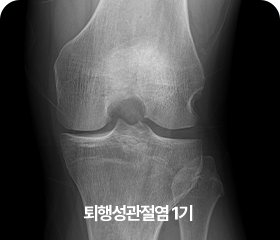

단계별 퇴행성 관절염 증상

1기